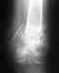

Здравствуйте! 28 декабря от удара кулаком об стену сломал 4-ю пястную кость, в травме сделали снимки (горизонтально и под 45 гр.), сказали без смещения, наложили лангету. 4 января сделали снимок, сказали заживает. 26 числа лангету сняли, сделали снимки (горизонтально и под 45 гр.), через пару дней по инициативе рентгенологов сделали вертикальный снимок. Резюме - консолидирующий перелом, разрабатывай. Через пару дней съездил на платную консультацию во Вредена, оказалось, что присутсвут вывих: 4 и 5 кости съехали назад и вверх, образуя горб. Сейчас делаю назначенные процедуры, но велики сомнения, что смогу полностью сжать кисть в кулак - ощущение, что пястные кости мешают друг другу. Подскажите, пожалуйста, следует ли требовать от травмпункта, чтобы мне дали направление на консультацию, а потом, по необходимости, и на операцию во институт Вредена, поскольку изначально диагноз "вывих" не был поставлен?